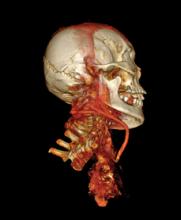

New research published in the June issue of Global Heart, the journal of the World Heart Federation, shows that there are no significant differences in the incidence or severity of atherosclerotic disease (narrowing of the arteries with fatty deposits) between ancient and modern people, proving that atherosclerosis is not just a disease of modern times. The journal included three articles [1,2,3] on the finding of the Horus study, which used computed tomography (CT) scans from ancient mummies to compare arterial calcification caused by Horus atherosclerosis.